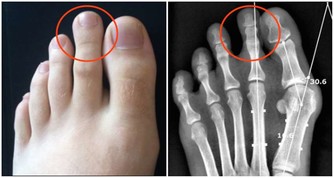

中老年人在做骨密度檢查時,若骨量減少9%以下為骨量正常,骨量減少9%~19%為骨量減少,骨量減少29%~39%則為骨質疏鬆、骨折危象。